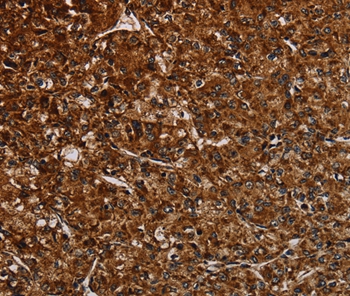

图片:

Immunohistochemical analysis of paraffin-embedded Human lung cancer tissue using #37755 at dilution 1/50.

,

Immunohistochemical analysis of paraffin-embedded Human prostate cancer tissue using #37755 at dilution 1/50.